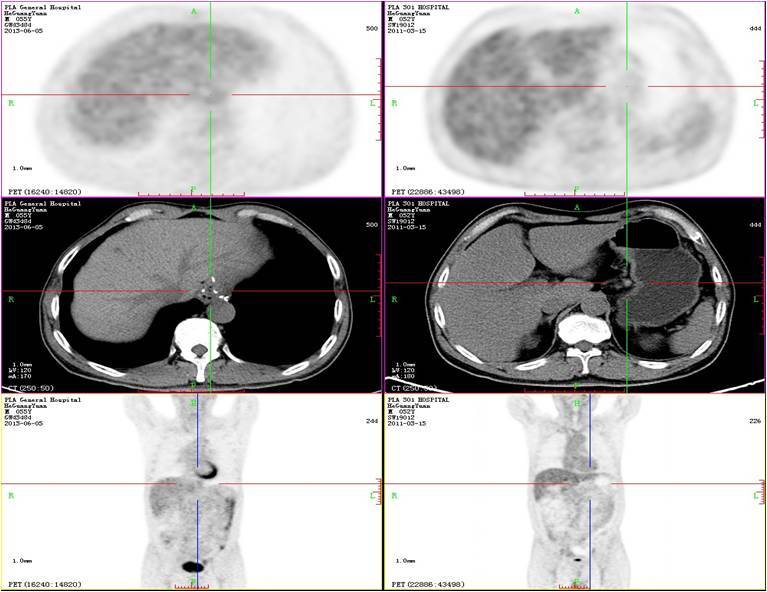

鉴于术后病理免疫组化HER-2(+++),2011年12月至2012年04月继续输注曲妥珠单抗5次。2012年6月至今每3-6月定期复查,均未见复发及转移,末次复查时间为2015年11月25日,疗效评价仍为维持PR,目前患者PFS已达6年余。

2013年6月PET/CT检查

2013年12月复查

2015年10月复查

胃癌患者在发生肝脏转移时往往伴随肝脏以外的转移。如果没有肝外转移,且病灶位于肝脏一叶或直径小于4cm的转移灶及肝脏孤立转移病灶,胃部原发病灶可切除,经一线化疗病情缓解且身体状况良好可以考虑与原发灶一并切除。对于伴有肝外转移者,一般以全身化疗为主。如果全身化疗后肝部病灶仍进展,且有破裂出血风险或产生压迫症状等,可以考虑行肝转移射频消融、肝动脉化疗灌注/肝动脉化疗栓塞等治疗。该患者无上述情况,以全身治疗为主,局部肝脏病灶在长期稳定的状态下是可以考虑局部治疗的。我们MDT的经验是对于类似病灶还是建议进行局部处理的,一方面可以进一步明确转移灶病理诊断,另一方面彻底消除病灶也是有临床获益的,而且影像学的CR/PR未必是病理学的CR/PR。由于患者对局部有些顾虑,加之病灶一直稳定,PET/CT 也未显示代谢,所以一直未进行处理,密切观察中,从目前随访长达5年的时间患者肝部病灶一直处于稳定状态中,加之PET/CT也未显示代谢,肝部病灶有可能完全灭活。

对于晚期肿瘤患者,我们治疗的目标是延长生存期和提高病人生活质量。如果患者转移淋巴结压迫血管、气管、神经等,出现水肿、憋气及疼痛等症状时需要局部处理改善症状。该患者左锁骨上、腋窝、腹腔淋巴结经治疗后消失,且没有任何临床症状,PET/CT 也未显示代谢,所以暂不需处理。